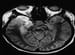

HSV-1 is a common cause of fatal encephalitis in the US, with a mortality rate 60-80%. Fewer than 10% of patients are left without significant neurologic sequelae.